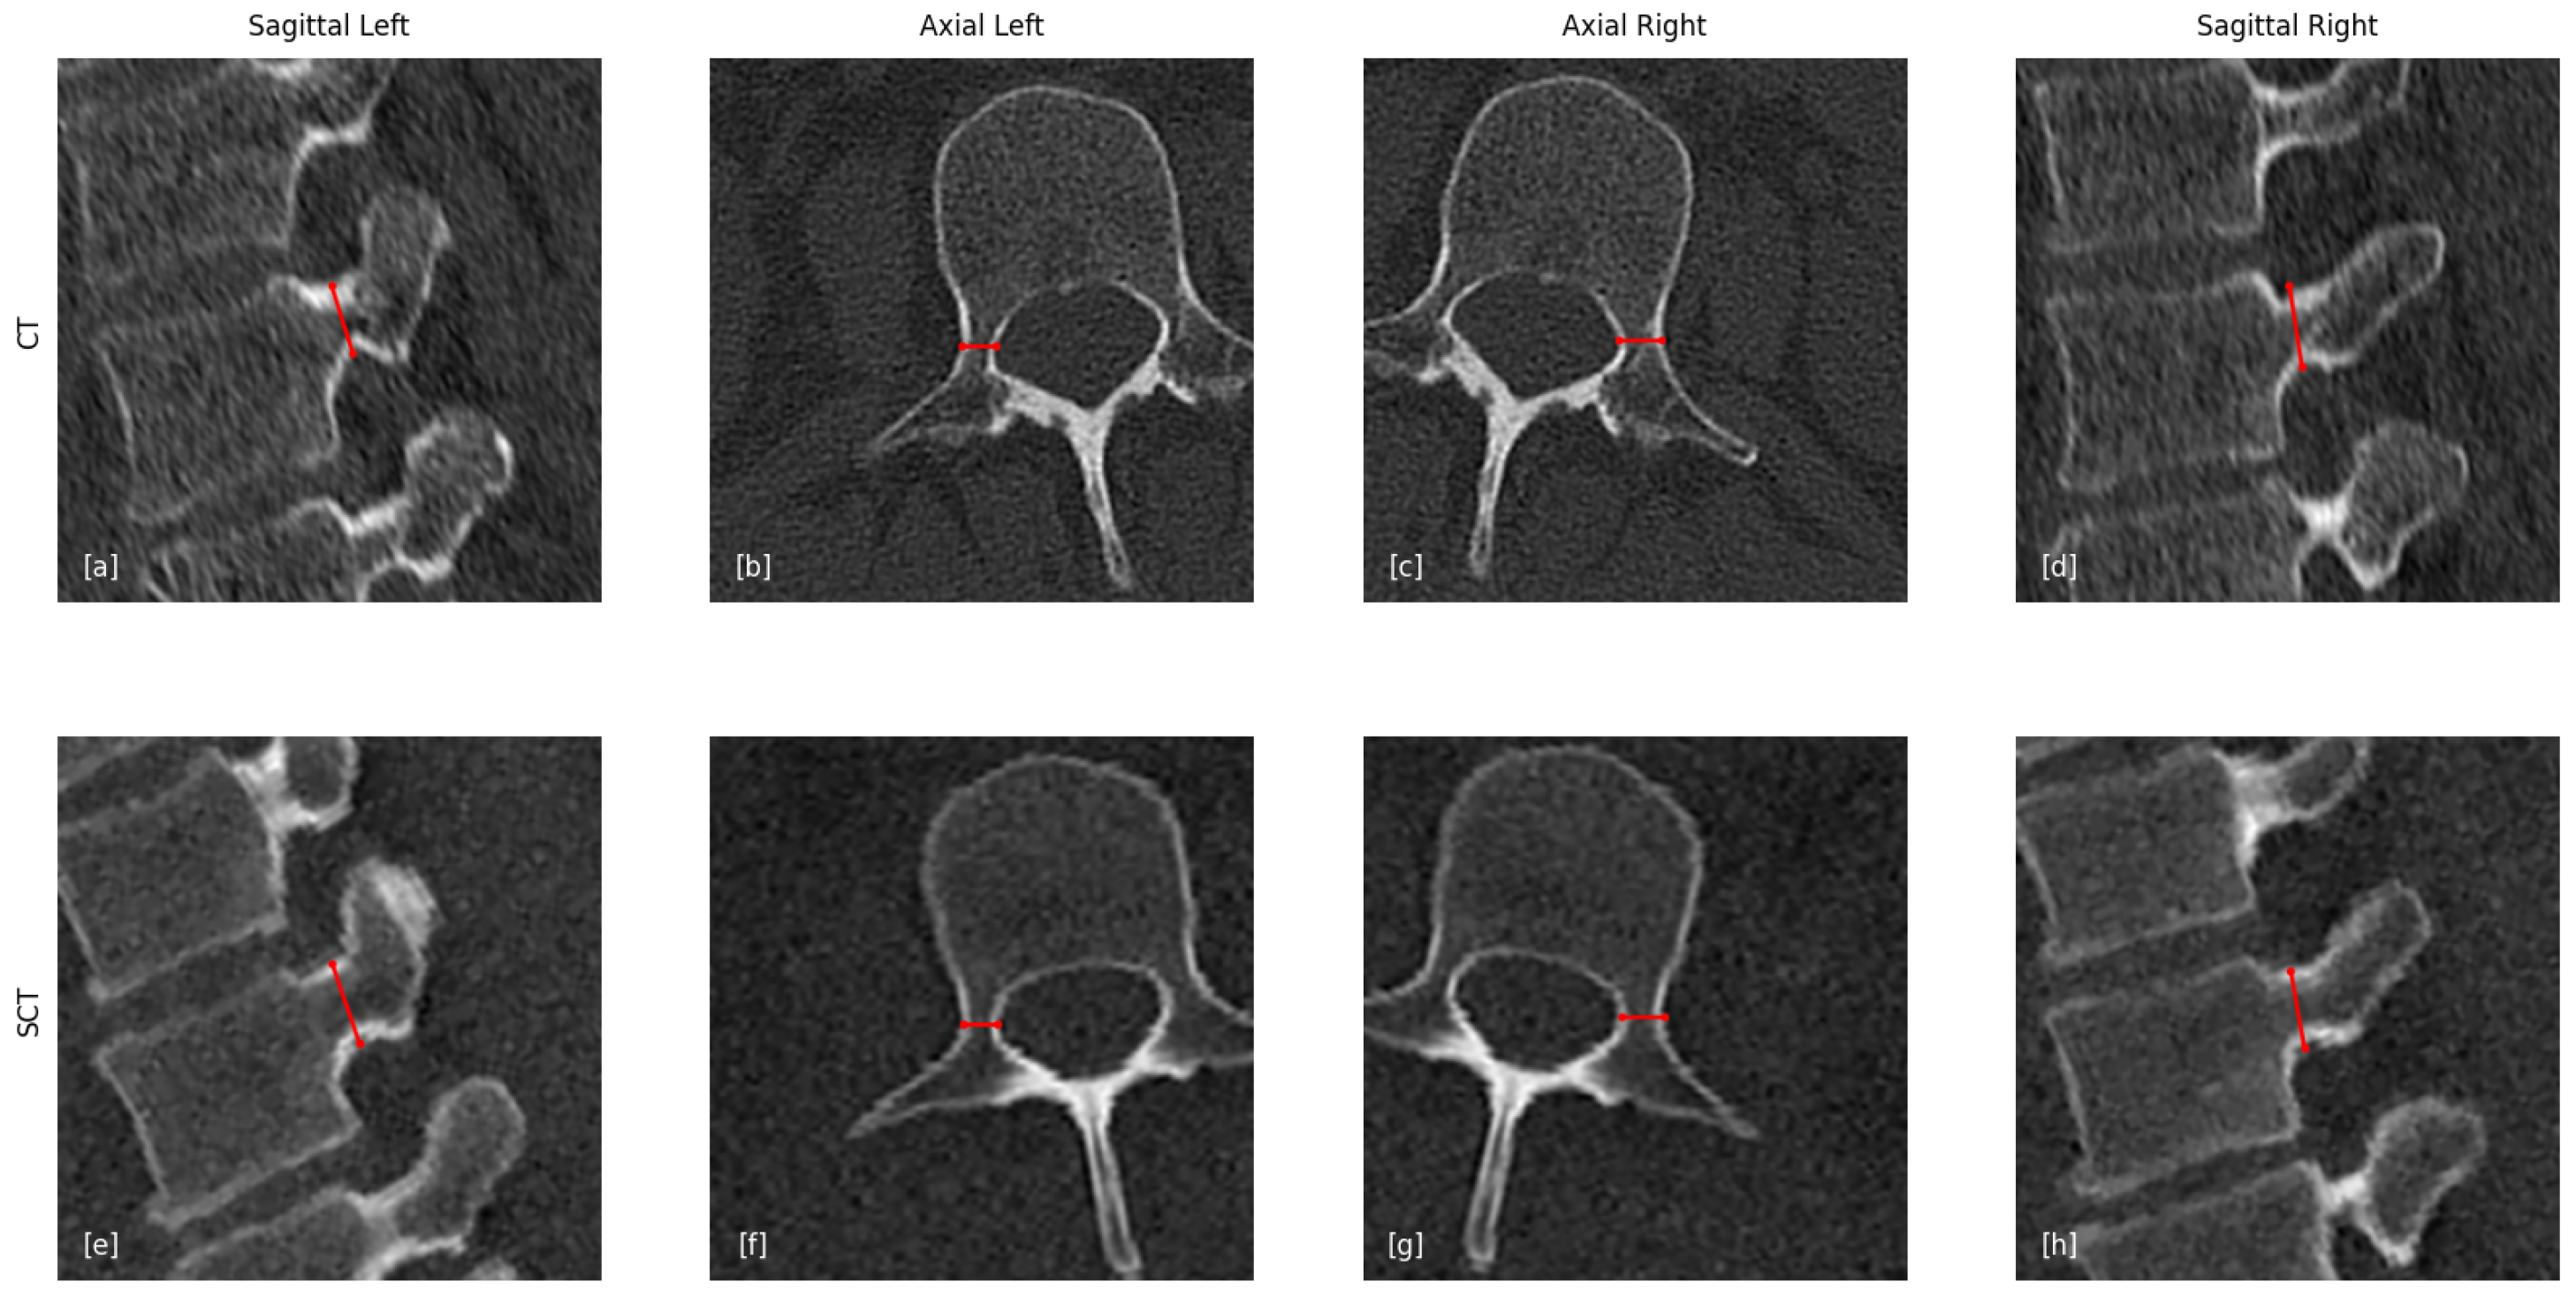

- Identification of the optimal pedicle screw trajectory;

- Selection of the narrowest cross-sectional plane along this trajectory;

- Measurement of pedicle width and height within this plane.